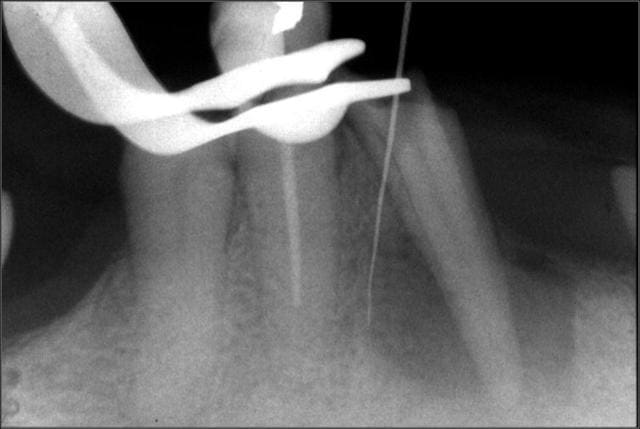

Voici un cas de fracture compacteur.

Utiliser un mac spaden dans ce genre de cas était une bêtise.

Aprés beaucoup d'efforts pour perméabliser les 2 cannaux et les préparer, c'est trop dommage de gacher le résultat en cassant un compacteur.

Cela ne m'a pas gêné pour desobturer et faire l'empreinte pour l'inlay-core, mais la condensation de la gutta au niveau apical n'a pas été terrible.

C'est d'ailleurs un des cas qui m' a décidé à utiliser de temps en temps le thermafill.